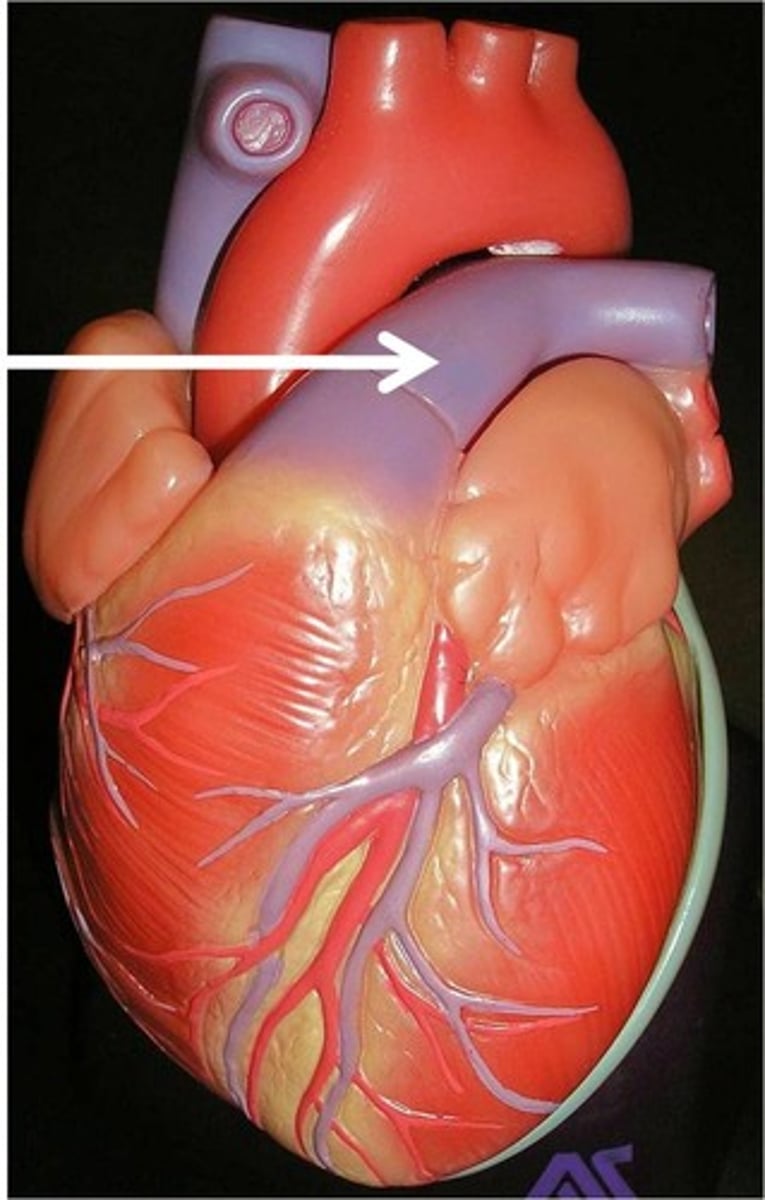

Left coronary artery

structure. On the coronary sulcus.

Left anterior descending artery

Structure. In the anterior interventricular sulcus.

circumflex artery

structure.